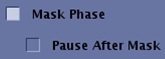

Mask Phase and Pause After Mask

Select Mask Phase to create a mask phase and select Pause after Mask to pause the scan after the mask phase. Series Per Phase